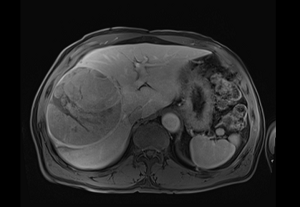

The 15cm hepatocellular carcinoma (HCC) tumour is the largest Mater Private Hospital Brisbane liver surgeon Dr Joel Lewin has removed from a patient at the hospital.

“The tumour occupied the majority of the right side of the liver, making surgical resection challenging,” Dr Lewin said.

He said though often such liver resections can be performed keyhole (laparoscopic or robotic), Mr Tibbetts’ case required an open approach due to the size of the tumour.

“I had more scans just before having surgery and the mass had become so large it was creeping up into my diaphragm.”